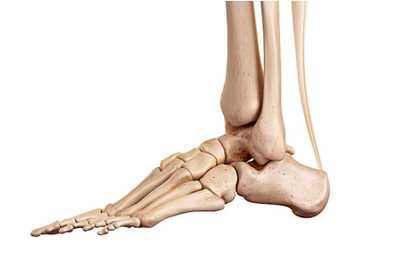

Чтобы понять механизм переломов плюсневых костей, вероятно, лучше начать с краткого объяснения анатомии стопы.

Стопа человека состоит из 26 костей:

- 5 плюсневых костей. Это трубчатые кости, которые расположены между костями предплюсны и фалангами пальцев. Функционально плюсневые кости играют важную роль в движении, выполняя роль рычага при движениях стопы (шаги, бег, прыжки).

- 14 фаланг пальцев. Первый палец состоит из двух фаланг, остальные пальцы - из трех.

- 3 клиновидные кости. Расположены между ладьевидной костью и первыми тремя плюсневыми костями.

- Кубовидная кость

- Ладьевидная кость

- Таранная кость

- Пяточная кость

Все вместе кости стопы образуют очень сложный механизм, который компенсирует колоссальные нагрузки в течение дня и помогает гасить удары при каждом шаге.

Стопа состоит из 28 костей и 34 суставов, из них 18 выпукло-вогнутые и 16 плоские. Все кости объединены в предплюсну, плюсну и пальцы. Кости предплюсны следующие: таранная, пяточная, кубовидная, ладьевидная, 1, 2, 3 клиновидные; кости плюсны: 1, 2, 3, 4 и 5. Все пять пальцев содержат 14 костей: у большого пальца имеется 2 фаланги, а у 2, 3, 4 и 5 пальцев — по 3 фаланги. Положение стопы в кинематической цепи нижней конечности связано с положением голени. Во время роста скелета вальгус стопы и низкий свод способствуют вторичному повороту бедра и коленного сустава во внутрь. После окончания роста высота свода и угол между большеберцовой и пяточной костями влияют на положение оси коленного сустава во фронтальной плоскости. Чем ниже свод стопы, тем больше ее вальгус, тем сильнее вальгус коленного сустава и тем сильнее наклонена голень во внутрь. Вальгус способствует пронации стопы, растяжению связок по внутренней поверхности коленного и голеностопного суставов, а также подошвенного апоневроза, что влияет на функцию всей нижней конечности.

Кости стопы формируют продольную и поперечную арки или своды. Продольная арка находится в сагиттальной плоскости и имеет протяженность от пяточного бугра до плюсне-фаланговых суставов. Продольный свод стопы состоит из внутренней и наружной арок. Внутренняя арка включает в себя 5 костей: пяточная, таранная, ладьевидная, 1 клиновидная и 1 пястная. Наружная арка состоит их трех костей: пяточная, кубовиидная, 5 плюсневая. Свод имеет форму арки, которая образована жесткими костными полудугами и основанием в виде подошвенного апоневроза.